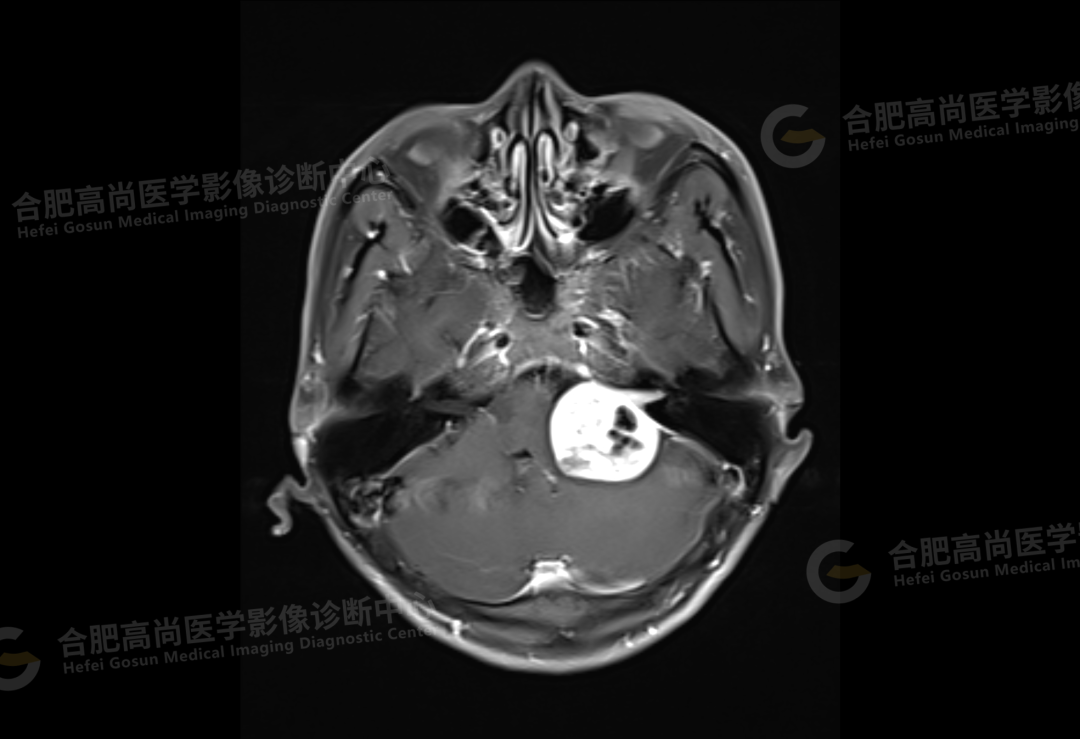

2、颅脑 MRI

颅脑 MRI 平扫+增强显示:左侧桥小脑角区可见类圆形囊实性异常信号,呈长 T1 长 T2 信号,flair 序列呈混杂高信号,内可见坏死囊变,大小约 3.0*3.5 cm,边界清晰,增强后病灶实性成分明显强化,囊变区未见明显强化,左侧内听道扩大,听神经增粗伴明显强化,病灶邻近小脑及桥脑受压推移变形,四脑室变形变窄,对侧桥小脑角区未见异常。

结论:左侧桥小脑角区占位,考虑听神经瘤。